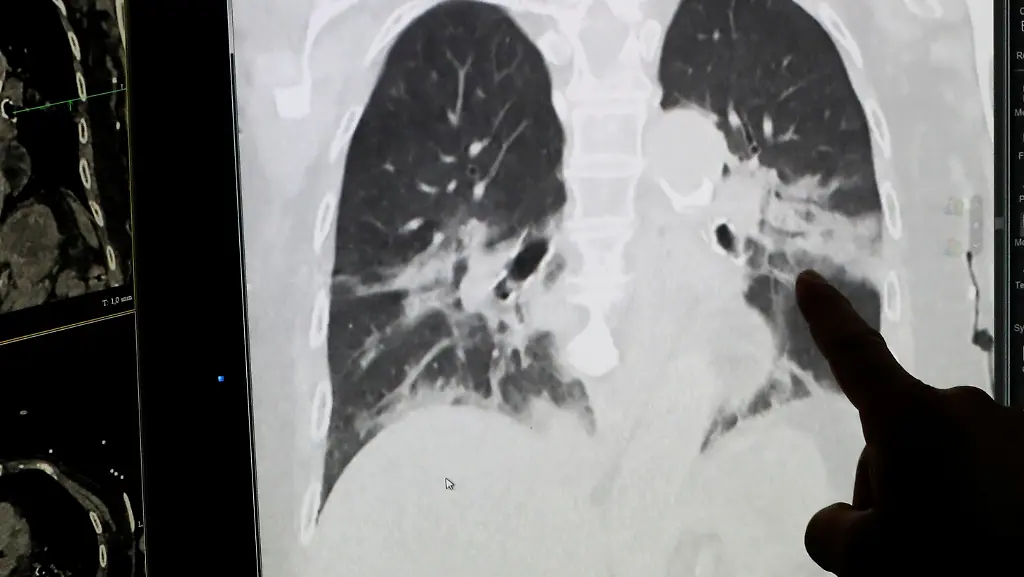

Ihre Erkrankungen lagen inzwischen fünf bis sechs Wochen zurück, bei der Kontrolle galten sie als klinisch gesund. In der Computertomographie der Lungen sahen die Organe aber alles andere als gesund aus. "In der Bildgebung wurden sie überhaupt nicht besser", berichtete Hartig dem italienischen Sender Rai. "Als Notfallmediziner mit 20 Jahren Erfahrung schluckt man, wenn man bei einem 40-jährigen Patienten so etwas sieht."

Bei zwei seiner Patienten trat unter Belastung ein deutliche Sauerstoffunterversorgung auf. Zwei weitere zeigten "sehr erregbare Bronchien wie beim Asthmatiker". Bei vier der sechs Patienten waren im Controll-CT immer noch deutliche Veränderungen im Gewebe zu sehen. Zuvor hatte Hartig bereits beschrieben, dass es bei Corona-Patienten eine "bemerkenswerte Diskrepanz zwischen den Befunden und dem Empfinden" gebe.

Junge Patienten "im besten Tauchalter" kämen zu Fuß in die Notaufnahme und wiesen normale Vitalparameter auf. Das heißt Herz- und Atemfrequenz sind unauffällig, ebenso wie Blutdruck und Körpertemperatur. Auf CT-Bildern seien dann aber "beidseitige Infiltrate" zu sehen. Hartig beschreibt das, "als ob man ein, zwei Tücher in einen Eimer Öl hängt und wieder rauszieht und aufhängt". Andere Patienten hätten eine erhöhte Atemfrequenz, die sie kaum selbst bemerkten, "obwohl sie derart schlechte Blutgase haben, dass man laut Lehrbuch unverzüglich an eine Intubation denken sollte".